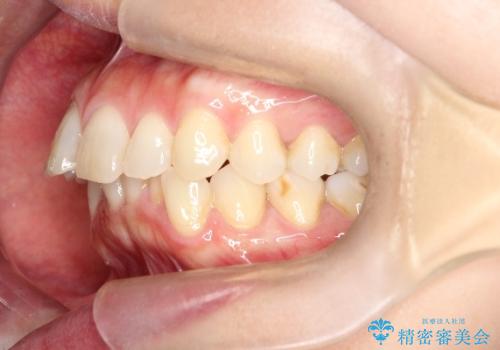

【インビザライン】前歯の凸凹を治したい

- 前歯の凸凹を主訴に来院されました。

臼歯部の遠心移動を行いながらスペースを作り、インビザラインにて前歯をきれいに並べることができました。

今回の治療計画では臼歯部の遠心移動とIPRを行っています。